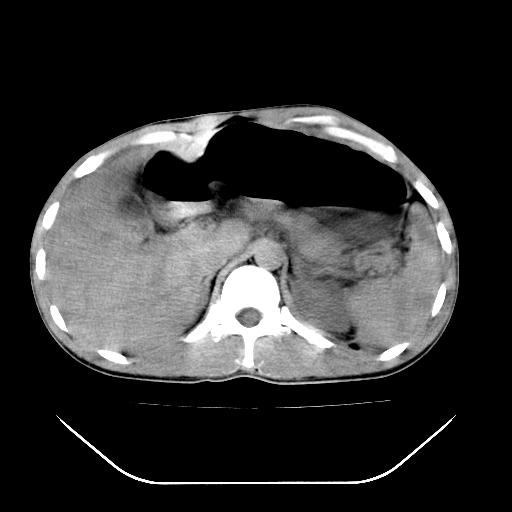

m-25y 高空堕落 12 月5号

12月7号病人尿量200ml/24h 急查双肾ct

左肾挫裂伤并肾周血肿;

肝肾间隙可见液区,建议手术探查;

支持:1、左肾挫裂伤并肾周血肿;

2、少量腹水;

3、左肾旋转不良;

4、反射性肠淤张。

3、反射性肠淤张。